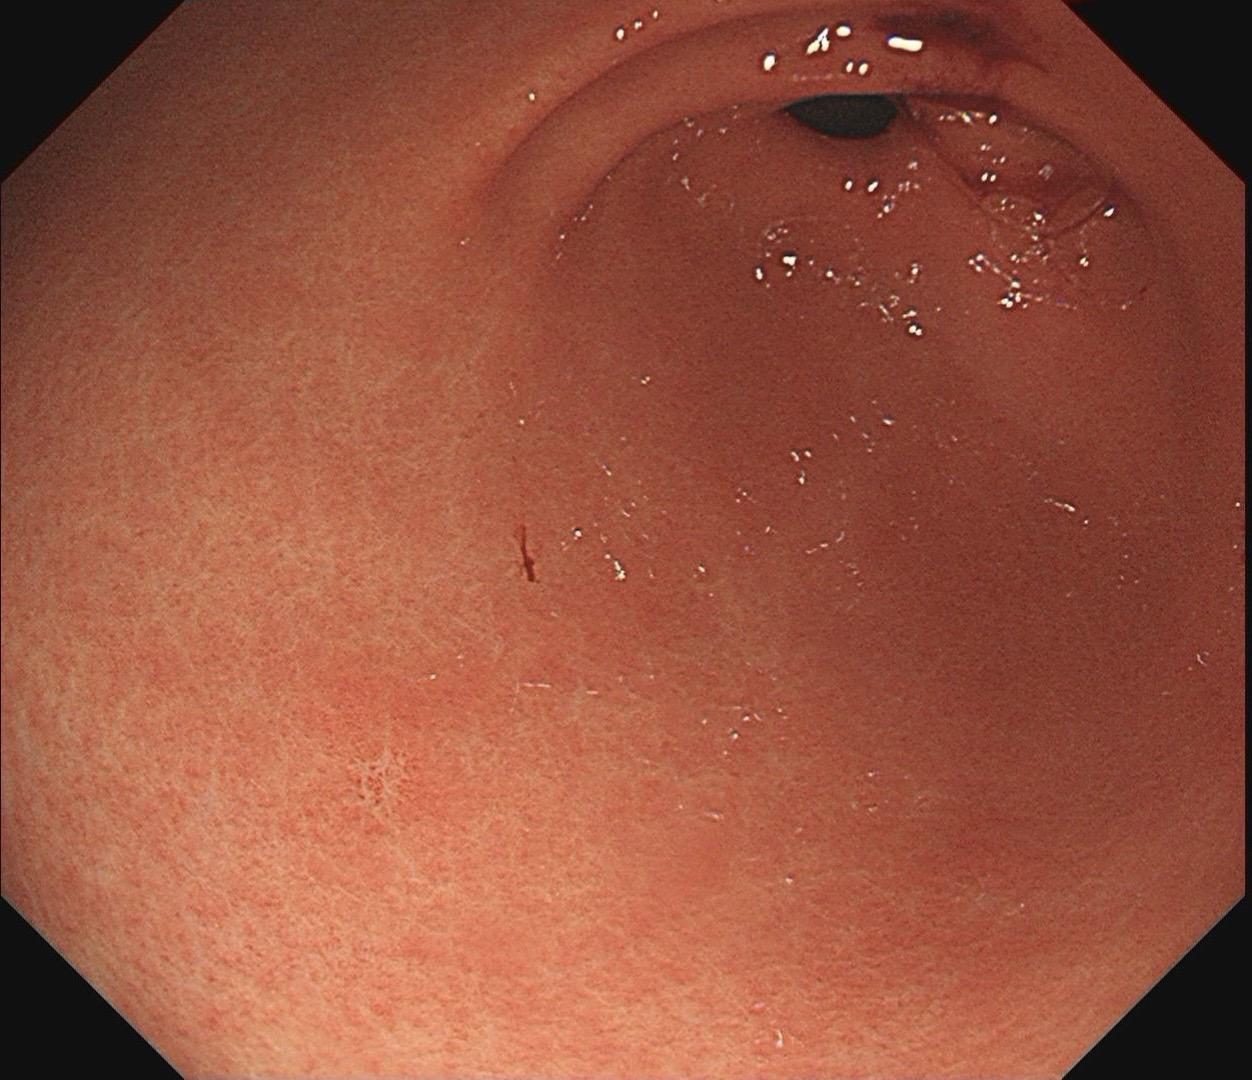

小小的糜烂一枚。这样的病灶,就算结果是阴性的,也很有意义~